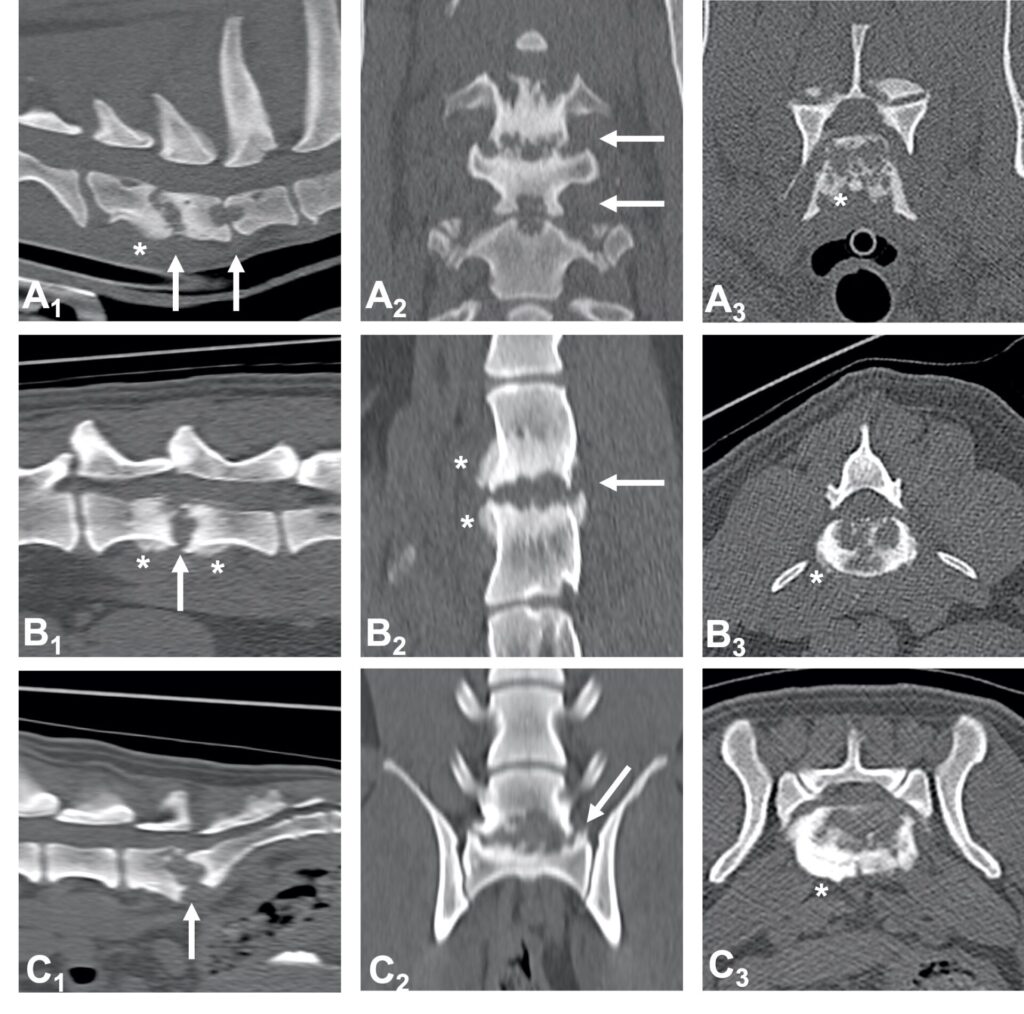

A radiograph of the spine will typically reveal damage to the vertebrae adjacent to the affected disc. The spine can become deformed and undergo bone changes as a result of chronic conditions. Radiographs may not show changes for 3-6 weeks after clinical signs begin, so if the first radiographs are normal, but the clinical signs are progressing, it is sensible to repeat them some time later.

When a typical lesion is detected, radiographs of the entire spine are recommended since some pets have multiple lesions. When a disc is infected, it degenerates and destroys the ends of adjacent vertebrae. There is evidence that these degenerative changes may weaken the vertebral column and make it more susceptible to pathologic fractures, which are caused by infection rather than trauma. As part of the healing process, the body may attempt to bridge the damaged area with bone, which may encroach on the spinal cord and nerve roots, resulting in further complications.

Imaging techniques such as computed tomography (CT) and magnetic resonance imaging (MRI) are more sensitive than plain radiography, particularly when it comes to detecting the problem early on.